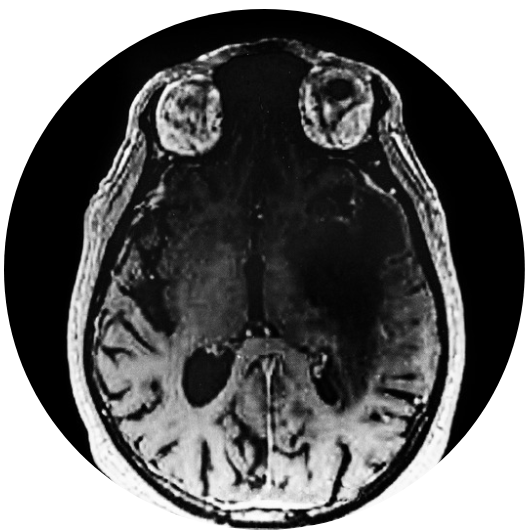

PIF neurologique

Convulsions, ataxie, douleurs cervicales, douleurs rachidiennes